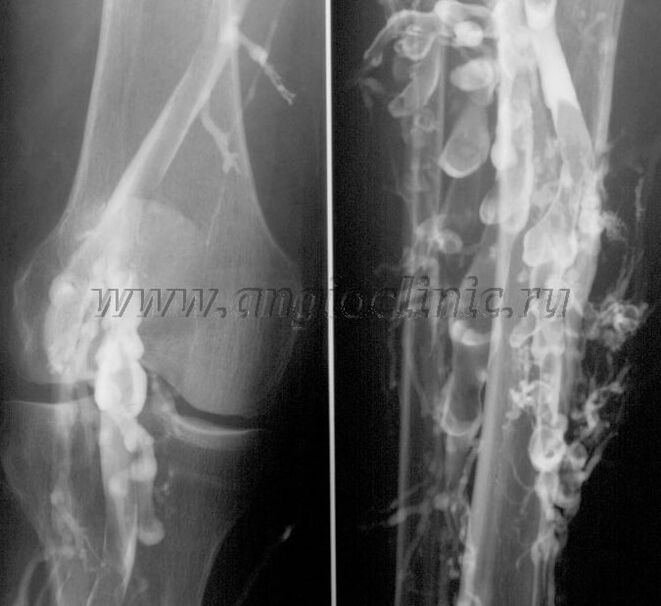

venography

Usually, ultrasound scanning is sufficient for the complete diagnosis of venous pathology, but in some cases it is necessary to study the relationship between the state of the deep and superficial venous system, especially in the case of varicose veins and secondary varicose vein recurrence.

In order to solve these problems, X-ray imaging examination is used.The saphenous vein is punctured and contrast medium is injected.Observe the movement of the contrast on the monitor of the X-ray machine and perform all necessary tests and projections.Currently, venography is rarely used for varicose veins.